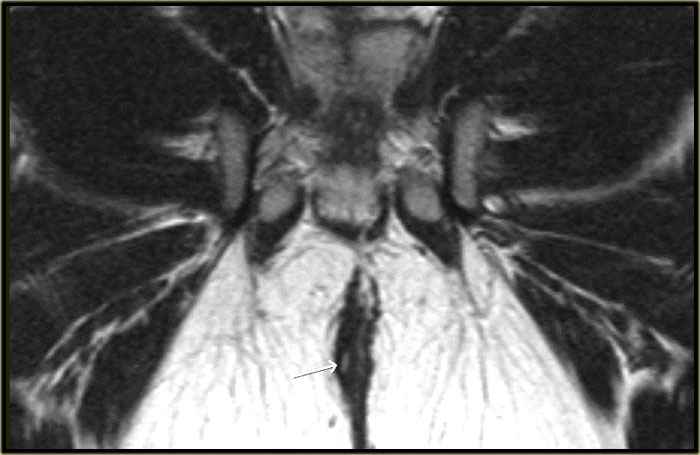

Bệnh nhân này đã được chẩn đoán trước đó là rò liên cơ thắt, với tổn thương niêm mạc ở vị trí 1 giờ.

Trong lòng đường rò có một cấu trúc dạng tuyến tính với tín hiệu thấp.

Đây là chỉ Seton đã được đặt vào để điều trị đường rò.